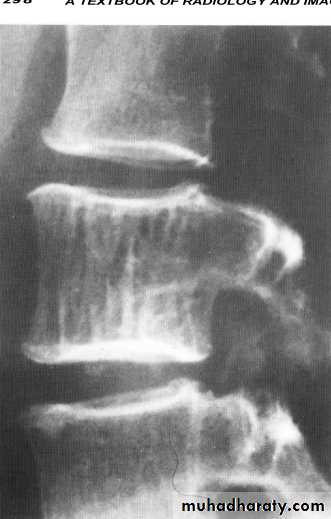

Spondylolysis and spondylolisthesis

Spondylolisthesis is a term denoting fore ward or backward movement of a vertebra relative to the vertebral segment below, typically due to spondylolysis (pars interarticularis defects) .Spondylolysis - “Spondylolysis is a defect in the pars interarticularis of the neural arch, the portion of the neural arch that connects the superior and inferior articular facet in which cause defect in the neck of scotty dog .

scotty dog sign refers to the normal appearance of the lumbar spine when seen on oblique radiographic projection. On oblique views, the posterior elements of vertebra form the figure of a Scotty dog with:

the transverse process being the nose

the pedicle forming the eye

the inferior articular facet being the front leg

the superior articular facet representing the ear

the pars interarticularis (the portion of the lamina that lies between the facets) equivalent to the neck of the dog.